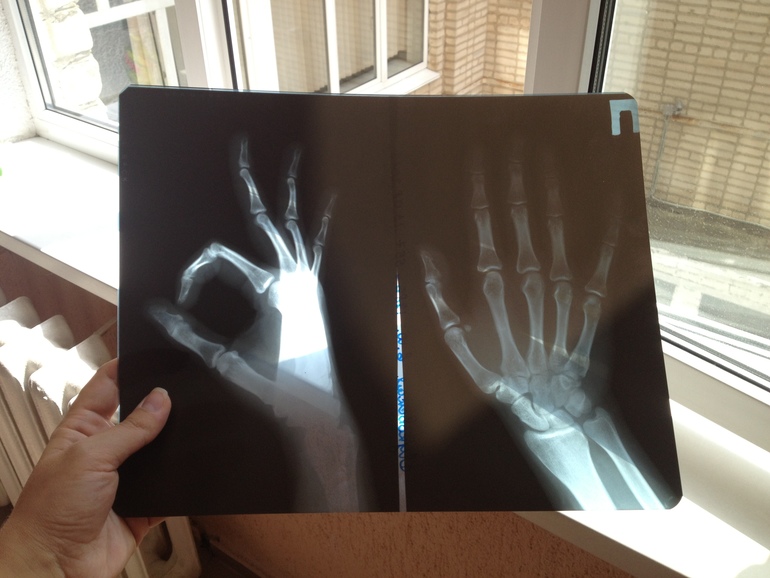

сума сойти 6 лет со стеклом жила, так и без руки можно было остаться если бы вдруг что, повезло вам что все таки вышло стеклышко

Нет, без руки я бы не осталась) Оно там прижилось у меня, и тихонечко сидело. А я все боялась в больницу идти. Трусиха еще та)))